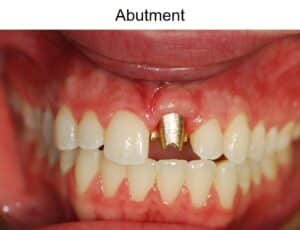

Custom abutment designed for optimal implant support

The Quality of the Dental Crown and Abutment Matter

In addition to the position of the implant itself, the quality of the dental crown and abutment that connects the crown to the implant can dramatically impact the longevity of the entire restoration.